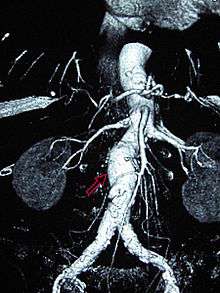

CT reconstruction image of an abdominal aortic aneurysm (white arrows) | |

Sagittal CT image of an AAA

Abdominal aortic aneurysms (3.4 cm)

An aortic aneurysm as seen on CT with a small area of remaining blood flow